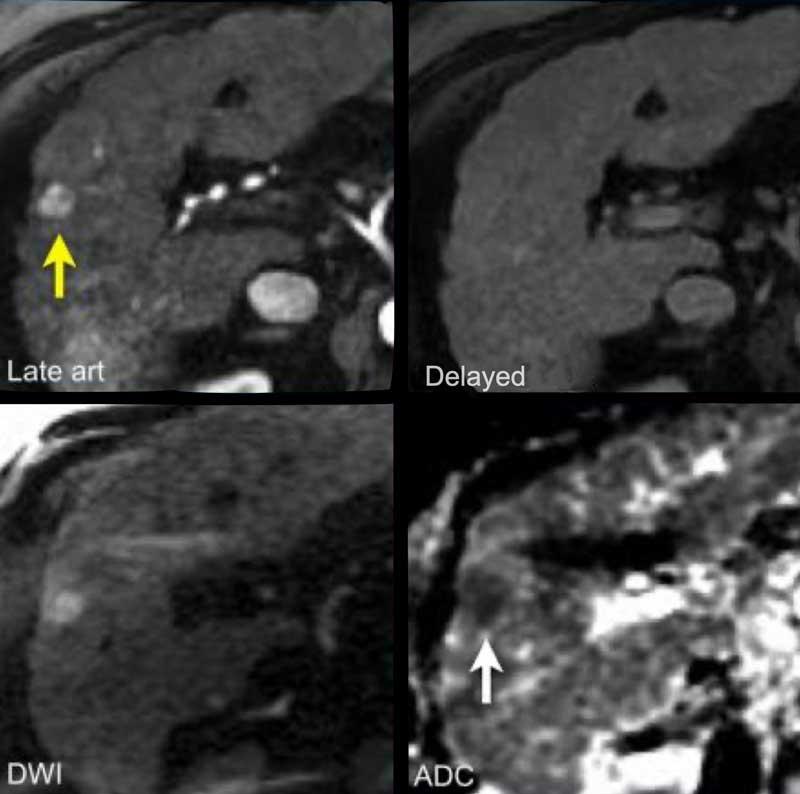

Hãy phân tích các hình ảnh MRI.

Đâu là các phát hiện chính và đâu là các phát hiện bổ sung?

Bạn sẽ cho điểm LI-RADS như thế nào?

Đặc điểm chính – làm cho đây là tổn thương LR-5:

- Tổn thương > 20mm

- APHE không dạng viền (non-rim APHE)

- Thải thuốc (washout)

Đặc điểm phụ trợ – sẽ được thảo luận sau:

- Hạn chế khuếch tán (mũi tên).

- Cấu trúc khảm (mosaic architecture) – thấy trên thì muộn.

Dưới đây là các phát hiện đã được điền vào bảng:

Đây là tổn thương LR-5.

Trong tổng số các tổn thương LR-5, 95% là HCC và 98% là ác tính.